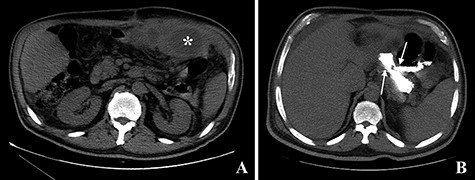

The computed tomography (CT) scan with oral contrast revealed a GGF (see Fig. 1). The upper gastrointestinal endoscopy confirmed a GGF and also demonstrated a stenosis of the gastro-jejunal anastomosis (GJA) (see Fig. 2).

Computed tomography with intravenous contrast images demonstrating a gastro-gastric fistula (arrows). A: axial reconstruction; B: sagittal reconstruction.

In December 2015, the patient presented to the emergency room complaining of pain in the left hypochondrium and anorexia. Upon physical examination, the only abnormal finding was tenderness to palpation of the left hypochondrium. The laboratory tests revealed an elevated white blood cells count (18.88 × 103/μL) and an elevated C-reactive protein (263.66 mg/L). A CT scan of the abdomen revealed a GGF with an associated abscess (see Fig. 8).

Computed tomography images. A: Image obtained prior to administration of contrast showing an abscess on the left upper quadrant of the abdomen (asterisk). B: Image obtained after administration of oral contrast showing progression of contrast through the gastro-jejunal anastomosis and through the gastro-gastric fistula (arrows).